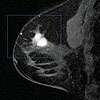

- Digital screening mammography with option for tomosynthesis

- Digital diagnostic mammography with option for tomosynthesis

- Diagnostic breast ultrasound

- Breast Magnetic Resonance Imaging (MRI)